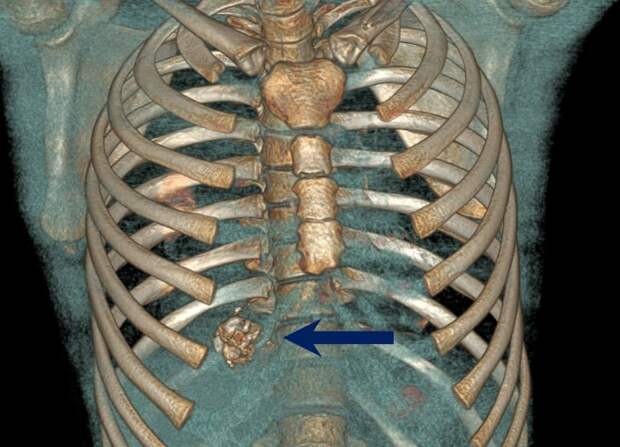

Заряд мгновенно пробил как куртку, так и кожу пострадавшего. Взрыв произошел уже внутри. После операции мальчика десять дней держали в реанимации. Теперь же его выписали.